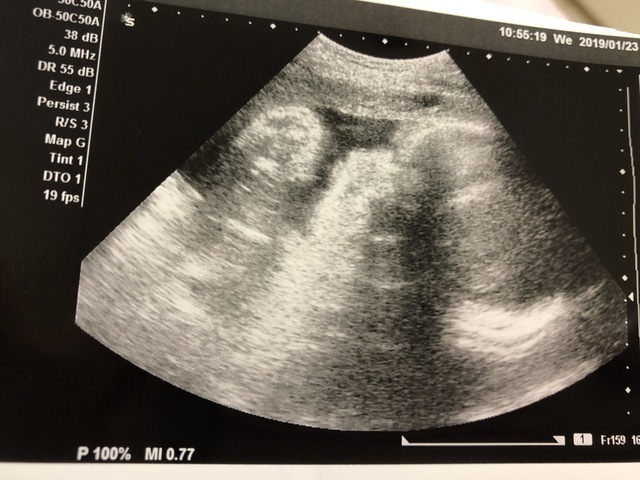

33週5日(33w5d・男の子)|みーひろ916 さん(30歳)

エコー写真撮影時のエピソード:

男の子と完全にわかる写真。 分かってはいましたが、もう一度先生に聞きました。 お顔が見えなかったのが残念です。

赤ちゃんが大きすぎるみたいで、なるべく早く産めるように頑張らないとしんどいと言われたので、里帰りしたらいっぱい体を動かして早く降りてくるように頑張ります。